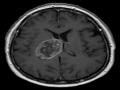

Technology :Study highlights importance of routinely imaging brain tumour patients

A team of researchers during a recent study explored the best way to monitor brain tumour. The team consisted of experts from the UK and stakeholders who met to discuss the value of routinely imaging brain tumour patients to assess their tumour treat ...

Health :Researchers shed light on routinely imaging brain tumour

A team of researchers explored the best way to monitor brain tumour. The article is the work of a large collaboration of UK experts and stakeholders who met to discuss the value of routinely imaging brain tumour patients to assess their tumour treatm ...